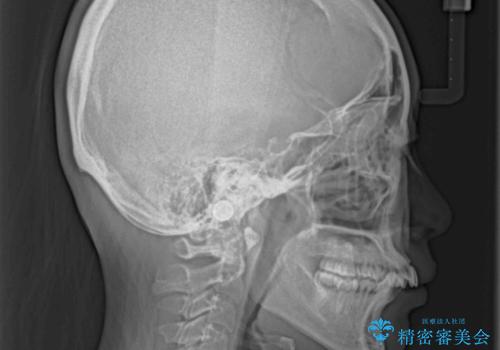

全顎的なデコボコと口元の突出感 ワイヤー装置での抜歯矯正で整った口元に

- 奥歯も含めて全体的なデコボコと前歯の突出感を気にして来院された患者様です。

上下左右第一小臼歯4本を抜歯し、ワイヤー装置にて矯正治療を行うこととしました。

想像以上に咬合力が強く、抜歯したスペースを閉じきるまでに長期間を要することとなりました。

前歯の突出感がなくなり、仕上がりには大変満足していただけました。